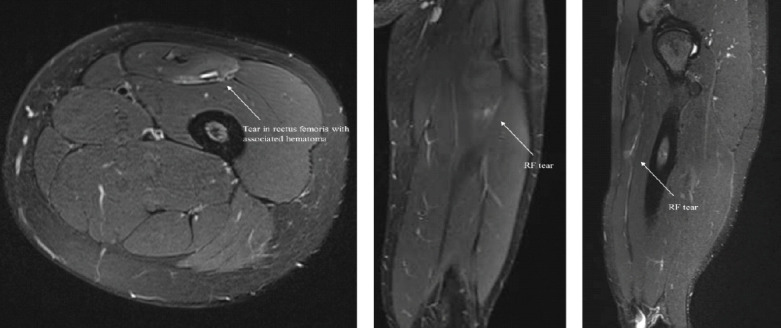

Case report: This case report describes a chronic injury to the indirect head of the RF in a 21-year-old softball player. The insidious onset was characterized by pain, edema, intramuscular hematoma, and decreased range of motion. The patient failed extensive conservative treatment, including 12 months of medication, PT, and activity modification. Surgical intervention and rehabilitation enabled the athlete to return to collegiate sport at the Division I level.